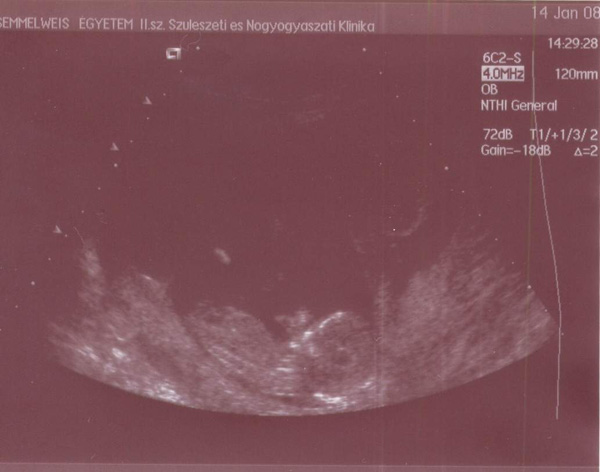

Íme 2 bemutatkozó fotó a kicsikről:

Kép Kép